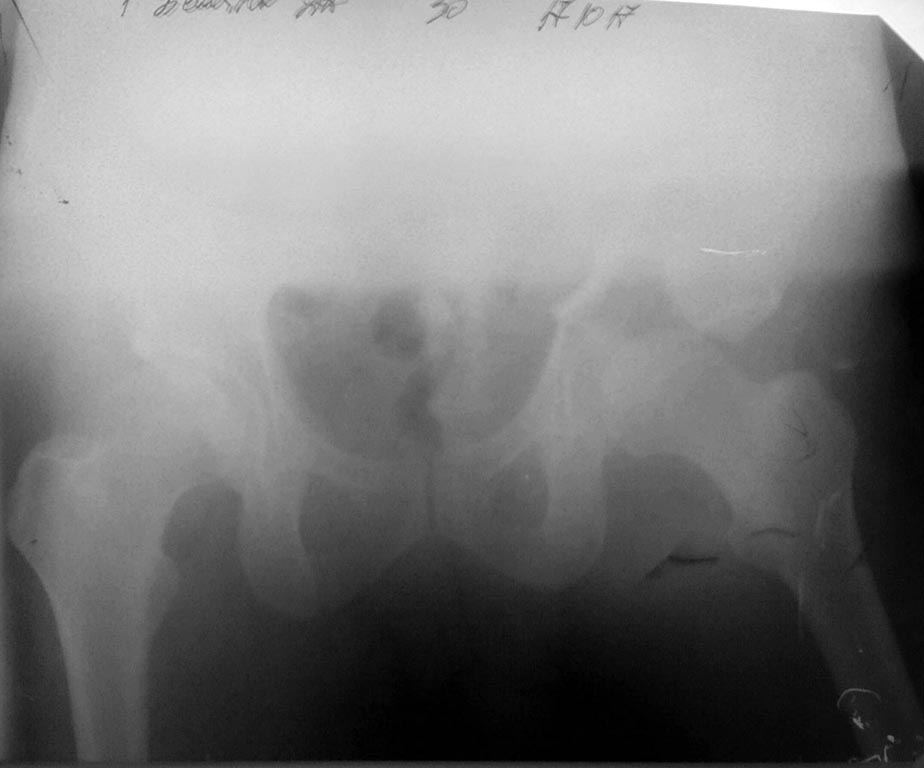

[Ortho] Перелом таза

Вчера (17.10.17) снимок на месте палатным аппаратом.

Положение отломков прежнее.

Кт в день поступления прилагаю.

Имя     : IMG_20171018_084519.jpg